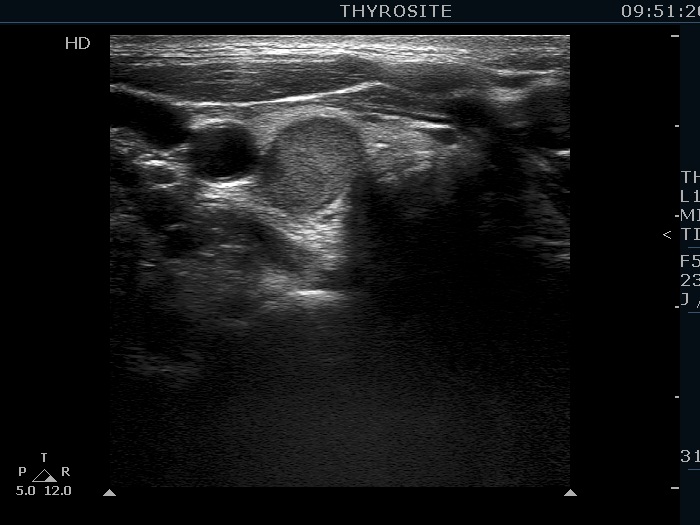

Ultrasonography. The thyroid was echonormal. There was a hypoechoic mass within the lower pole of the right lobe. The lesion was surrounded by thyroid tissue throughout.